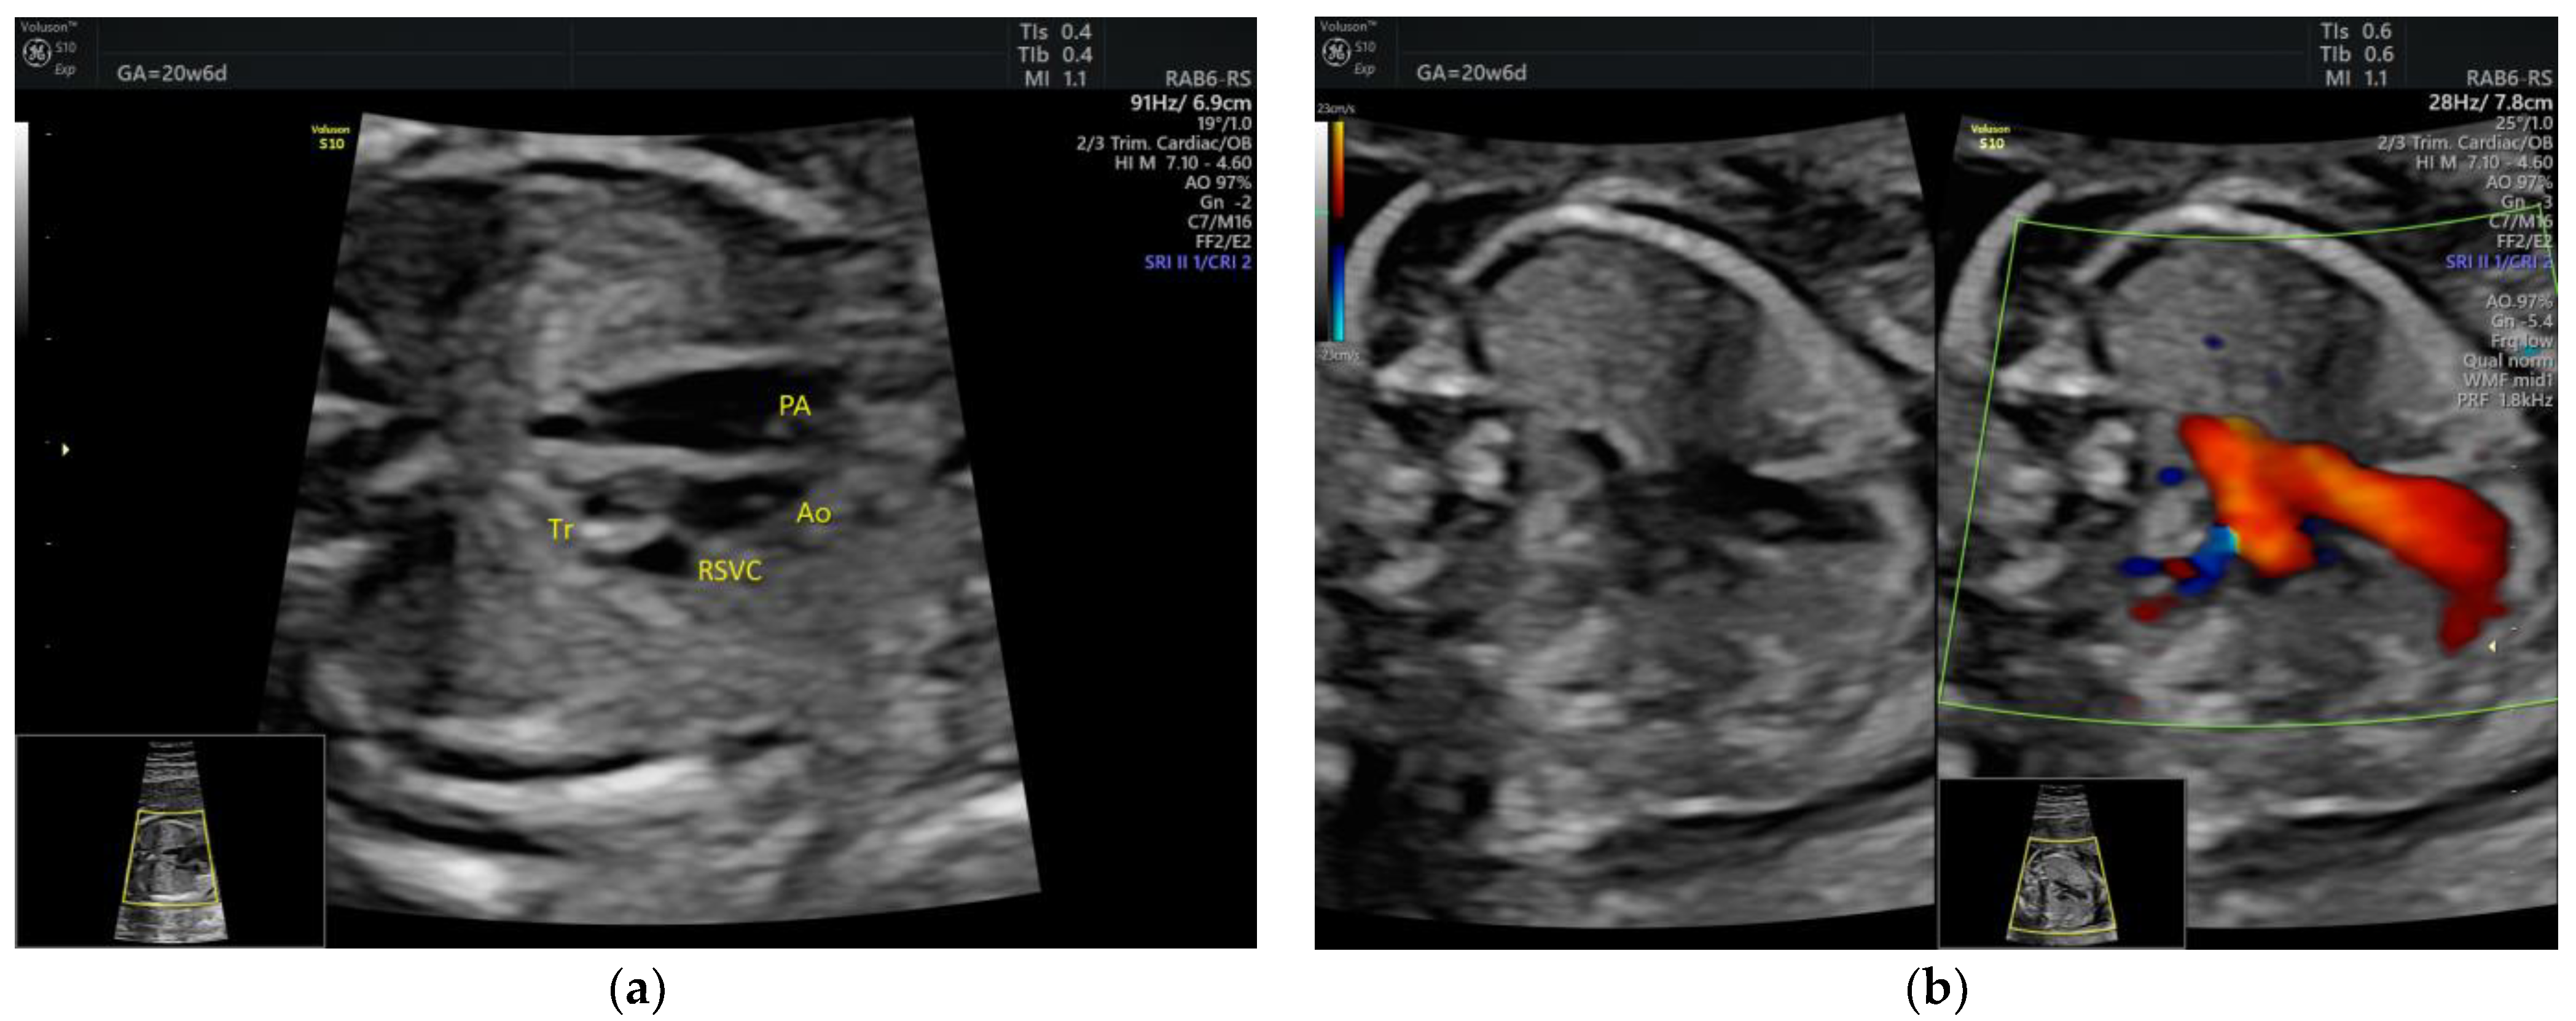

| Isolated ARSA | 6 | - | - | 3VT color | - | 0 | 6 | 0 | 2/5 |